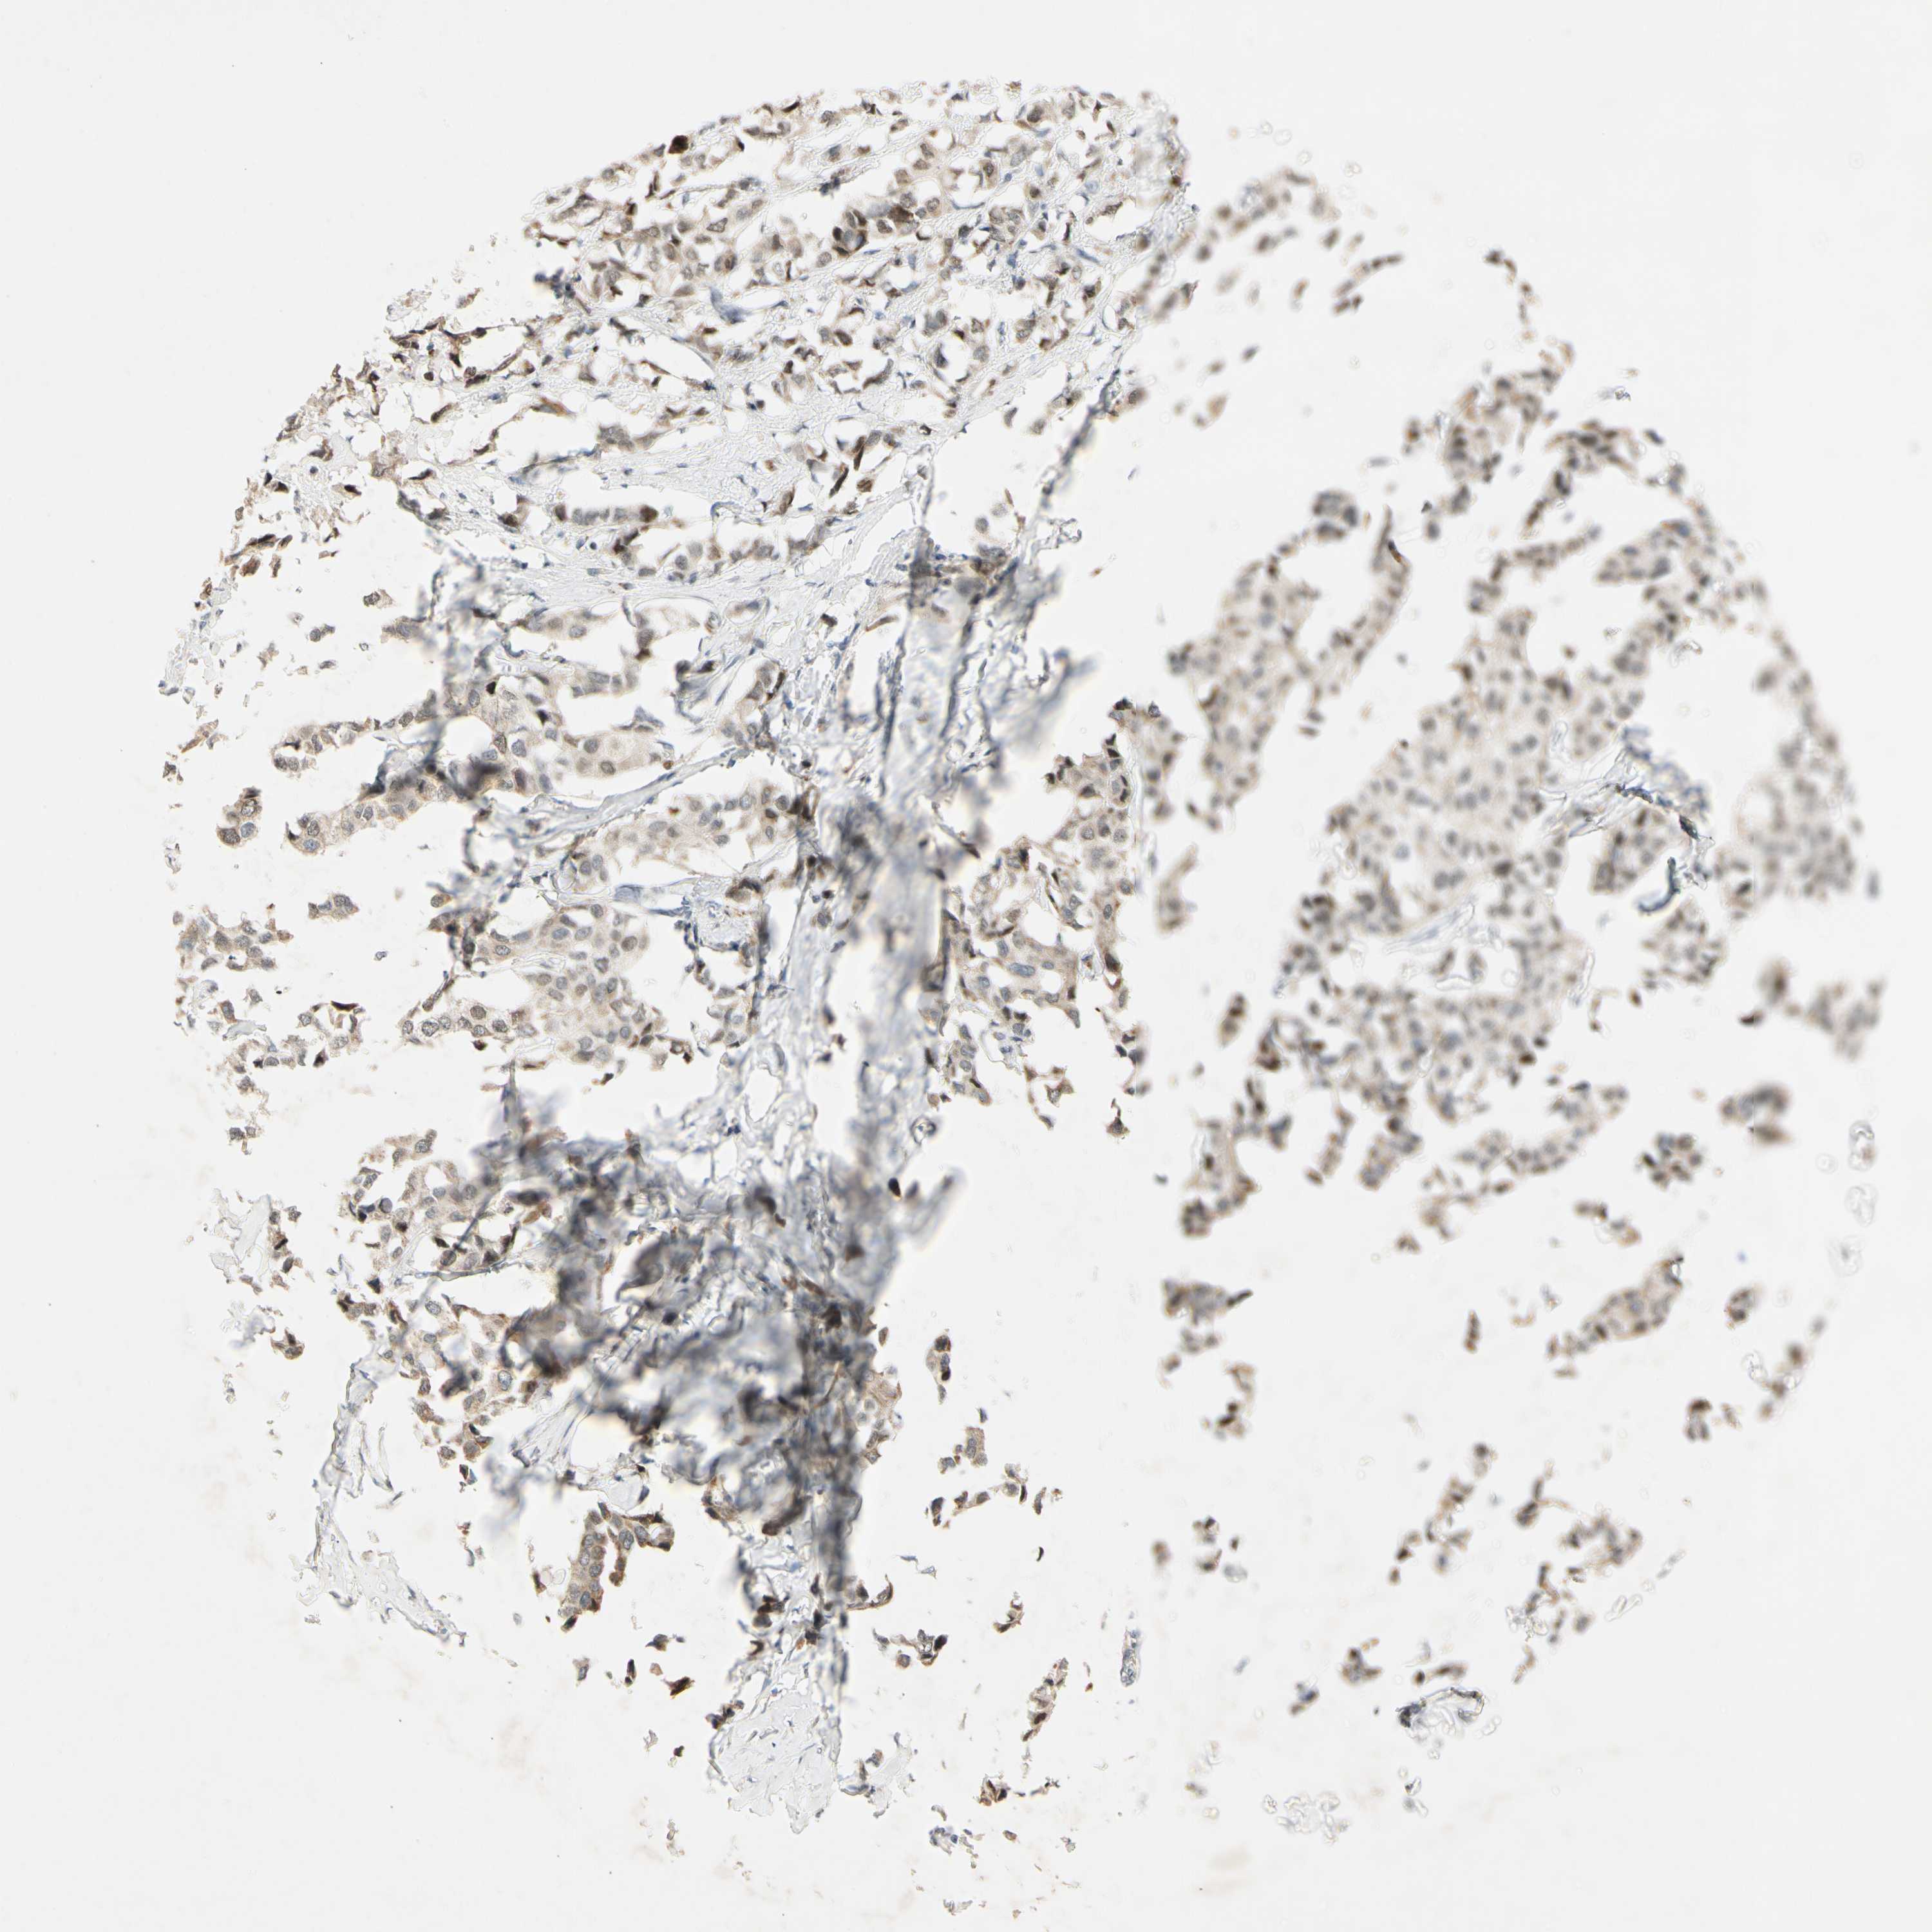

CANCER BREAST CANCER Show tissue menu

BRCA TCGA BRCA VALIDATION PROTEIN EXPRESSION